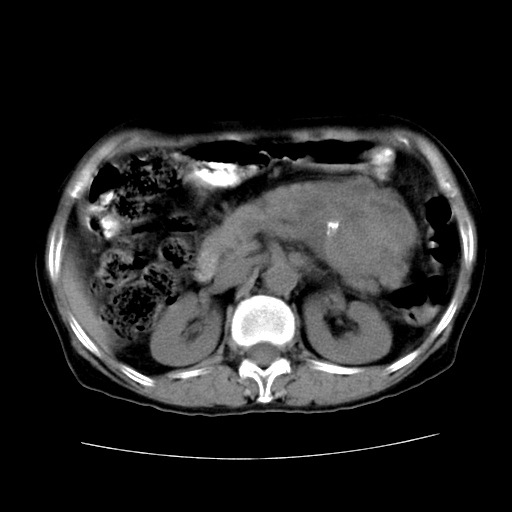

女性,72岁。

主诉中上腹部疼痛不适1年余。

胰腺尾部不规则巨大略低密度肿块,界限清楚,内密度不均,增强动脉期不均匀强化,门脉期明显退减并低于胰腺密度,肿瘤包埋于脾血管。多考虑;来源于胰腺尾部的“胰腺癌”。

胰腺尾部不规则巨大略低密度肿块,界限清楚,内密度不均,增强动脉期不均匀强化,门脉期明显退减并低于胰腺密度,肿瘤包埋于脾血管。多考虑;来源于胰腺尾部的“胰腺囊腺癌。

该例有几个特点需注意:

1.肿瘤大而边界清

2.内部有钙化

3.强化时间较长

4.这么大的肿瘤对周围的血管无侵犯

以上几条均与胰腺癌不符

故考虑:胰岛细胞癌

1、这个病例确实有点难。影像主要显示胰腺体尾部占位,我们当初也是诊断胰体尾部囊腺癌可能性大,而且读片会上也很多人这么诊断的。

2、手术所见:打开腹腔发现胃与胰腺体尾部可见肿块,大小约10×8×11cm,质硬,不可推动,周围血供丰富。术中诊断:胃肿瘤侵及胰腺体尾部。

1)、胃小弯侧胃肠间质瘤(考虑恶性),瘤体大小13.5×7×6.5cm,上下切缘阴性。

2)、胃小弯1只、幽门下2只淋巴结慢性炎。免疫组化:cd117(+)、cd34(+)、sma(+)、desmin(-)、s-100(-)、ki-67<10%(+).

4、这个肿瘤太大了,而且密度不均性强化,从这点我们应该不能单纯诊断胰腺癌,而应想到目前流行的胃肠道间质瘤。这个肿瘤主要发生于胃壁浆膜层,所以显示与胃壁关系不是很紧密,故而大多认为是胰腺癌。